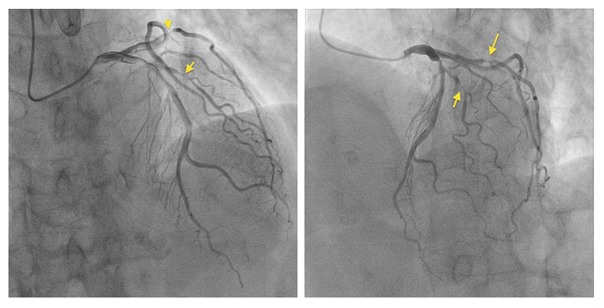

急性冠症候群の診断で緊急冠動脈造影検査が施行されました。右冠動脈に異常はありません。

冠動脈造影図

しかし、左冠動脈造影で、第一対角枝#9に90%、左冠動脈回旋枝鈍角枝#12に99%狭窄を認めました。

左冠動脈造影図